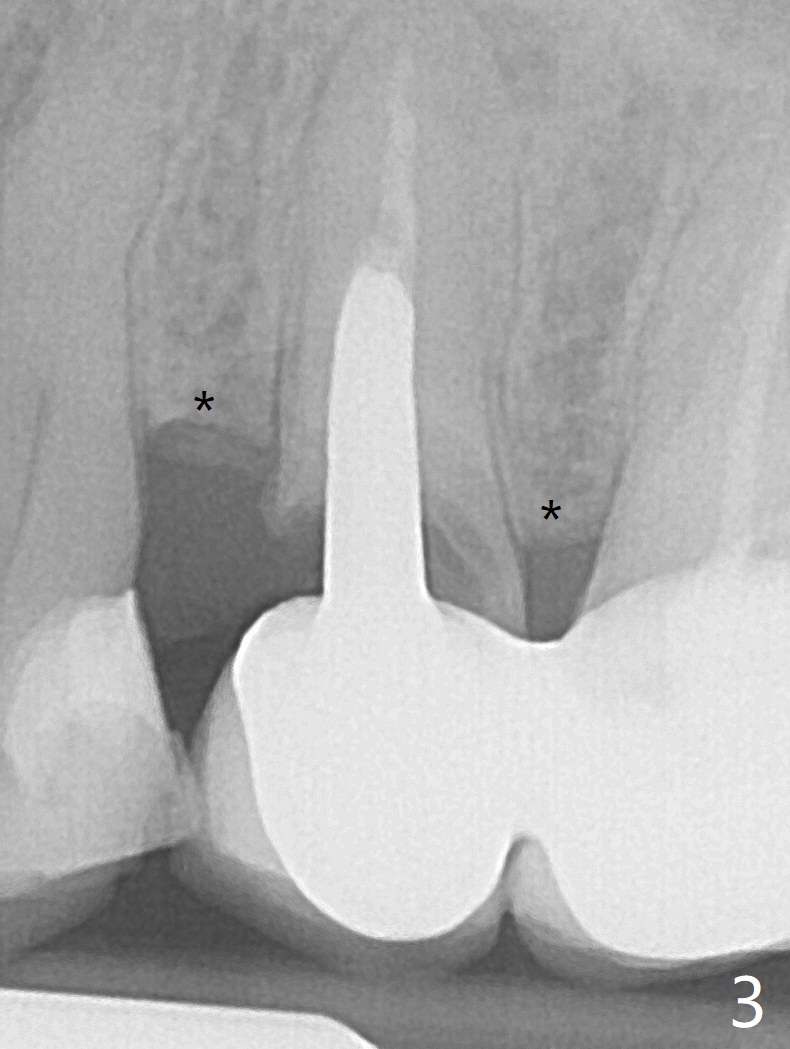

A 49-year-old woman has loose splinted crowns between #13 and 14. After removal of the crowns, the tooth #13 is found non-salvageable (Fig.1). A 4 or 4.5 x 8.5 or 10 mm implant should be able to achieve primary stability because of engagement of the implant into the mesial and distal walls of the socket and the sinus floor. Splinted provisional should provide with additional retention. There is no much need for socket shield, since there is no mesial or distal crestal bone loss (associated with food impaction). If the crown is short, there is no concern about buccal gingival recession. In fact the mesial papilla is more apical than the distal one (Fig.2 *), corresponding to the more apical crest (Fig.3 *). To prevent further mesial crestal loss post extraction, socket shield seems necessary. There appears that the implant is placed distal enough so that a small portion of the mesial root (Fig.4,5 R) is able to be saved. Fig.6 is the occlusal view of the residual root of the tooth #13. The mesial sheath will be kept (Fig.7,8, as compared to Fig.3).